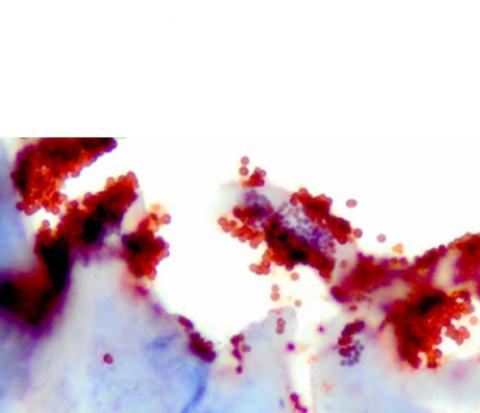

Staphylococcus aureus (S. aureus) notamment sa forme résistante, est devenu un problème de santé majeur car l’infection bactérienne peut être mortelle lorsqu’elle survient chez des patients immunodéprimés ou dans les environnements de plaies infectées. Certaines de ces bactéries deviennent résistantes à de nombreux antibiotiques, en particulier en formant des biofilms (Voir sur visuel en bleu) et il existe aujourd’hui un besoin considérable de nouvelles thérapies pour les éliminer.

Si la capacité des CSM à réduire l'inflammation a été suggérée par de nombreuses études, aucune étude n’avait encore évalué les effets du sécrétome des CSM sur les mécanismes de défense antimicrobienne des cellules de la peau ou sur des biofilms bactériens (Visuel du dessous).